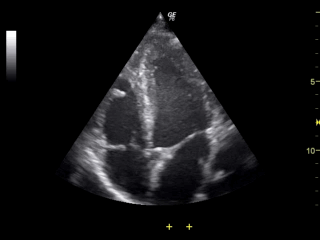

B 모드(Brightness mode)는 의료 초음파에서 가장 기본적이고 널리 사용되는 영상 표시 방식이다. 이는 반사되어 돌아온 초음파 신호의 강도(진폭)를 화면 위의 점의 밝기(휘도)로 변환하여 나타내는 원리를 사용한다. 즉, 강한 신호는 밝은 점으로, 약한 신호는 어두운 점으로 표시된다.하나의 초음파 탐촉자에서 나온 빔은 탐촉자와 직선상의 조직 정보만을 얻을 수 있어 1차원적인 정보만 표시하지만(A 모드), 여러 방향으로 초음파 빔을 빠르게 보내고 그 반사 신호들을 조합하면 신체의 2차원 단면 영상을 얻을 수 있다. 이렇게 얻어진 영상은 실시간으로 장기의 구조, 형태, 움직임 등을 관찰할 수 있게 해주어 진단에 매우 유용하다.

일반적으로 병원에서 '초음파 검사'라고 하면 대부분 이 B 모드 방식을 의미한다. 예를 들어, 심장 초음파 검사는 B 모드를 이용하여 심장의 구조, 심장 판막의 움직임, 심근의 수축력, 심방과 심실의 크기 등을 평가하는 데 필수적으로 사용된다.

심장 초음파 검사는 일반적으로 심장 전문의가 판독한다.[10] 이 검사는 몸 표면(체표)에서 초음파 기기를 이용하여 심장과 대혈관의 상태를 평가하는 방식으로 이루어진다. 하지만 심장 내부(심강)를 더 자세히 관찰해야 할 경우에는, 식도를 통해 초음파 기구를 삽입하는 경식도 심장 초음파 검사가 체표 검사보다 더 선명한 영상을 제공한다.6. 3. 소화기내과